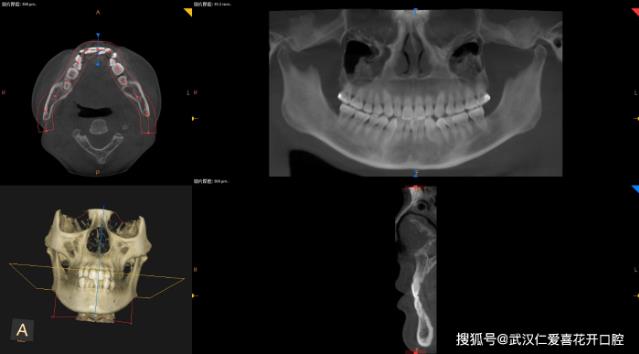

3,CBCT:这是一个三维立体的诊断,帮助医生查看颅骨内是否有埋伏牙,埋伏牙的位置和方向,以及周围三维结构上骨量的大小。它能够360度观察每颗牙齿与其他牙齿的毗邻关系,对于二维平面内的无法判断比邻关系的牙齿,最好的方法就是拍摄CBCT来直观地判断牙根被骨壁包绕的情况。李主任之前发的案例也有提到过,在患者牙槽骨薄、或者需要大量内收的情况下,都可以借助CBCT来帮助医生设计矫正方案。

CBCT